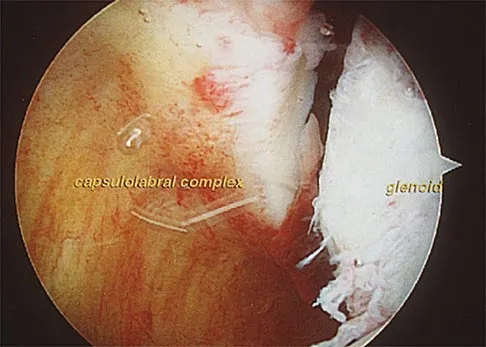

An 18-year-old hockey player sustains an acute anterior shoulder dislocation that requires manual reduction. At arthroscopy, the lesion shown in Figure 24 will be observed in what percent of patients?

Explanation:

The clinical photograph shows an acute capsulolabral avulsion from the anterior glenoid, also referred to as a Perthes-Bankart lesion. In patients who sustain an acute dislocation that requires a manual reduction, this pathologic lesion is observed with high frequency. In several research studies, it has been visualized in 80% to 95% of patients at arthroscopy. Taylor DC, Arciero RA: Pathologic changes associated with shoulder dislocations: Arthroscopic and physical examination findings in first-time, traumatic anterior dislocations. Am J Sports Med 1997;25:306-311.